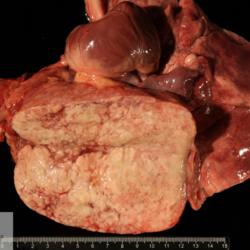

Pàgina anterior de 637 Pàgina següent 3181 total Bovine Specie: Bovine Organ: Trachea Lesion: Tracheitis Lesion modifier: Tracheitis - Granulomatous Disease: Tuberculosis Position: 253 (1 views) Ovine Specie: Ovine Organ: Lung Lesion: Pneumonia Lesion modifier: Pneumonia - Granulomatous Disease: Tuberculosis Position: 59 (4 views) Feline Specie: Feline Organ: Lung Lesion: Pneumonia Lesion modifier: Pneumonia - Granulomatous Disease: Tuberculosis Not viewed Feline Specie: Feline Organ: Lung Lesion: Pneumonia Lesion modifier: Pneumonia - Granulomatous Disease: Tuberculosis Not viewed Canine Specie: Canine Organ: Lung Lesion: Carcinoma Lesion modifier: Carcinoma - Adenocarcinoma Disease: - Files/Expedient: N-103/15 Position: 253 (1 views) Pàgina anterior de 637 Pàgina següent Títol Select...Avian (Exotic) (110)Avian (Poultry) (76)Bovine (317)Canine (935)Caprine (47)Equine (257)Feline (326)Ferret (19)General (127)Marine mammal (22)Non-human primate (20)Ovine (328)Porcine (379)Rabbit (61)Reptile (38)Rodent (28)Wildlife (91) Format Select...- (60)Abomasum (37)Adrenal gland (10)Blood (7)Blood vessel (50)Body as a whole (19)Bone (57)Bone marrow (21)Brain (93)Cloaca (1)Diaphragm (2)Ear (5)Esophagus (39)Eye (16)Fetus (12)Gallbladder (23)Gizzard (2)Heart (265)Intestine (356)Joint (32)Kidney (443)Larynx (5)Liver (326)Lung (264)Lymph node (91)Mammary gland (10)Mediastinum (1)Muscle (22)Nasal cavity (22)Nerve (7)Omasum (5)Oral cavity (63)Ovary (14)Oviduct (8)Pancreas (7)Parathyroid (5)Penis (10)Peritoneum (65)Pharynx (9)Pituitary gland (6)Placenta (7)Prostate (8)Proventriculus (3)Reticulum (1)Rumen (28)Sinus (7)Skin (181)Spinal cord (15)Spleen (105)Stomach (125)Teeth (1)Testicle (11)Thoracic cavity (31)Thymus (13)Thyroid gland (5)Tongue (32)Tonsils (11)Trachea (11)Urethra (5)Urinay bladder (61)Uterus (27)Vagina (1)Vulva (1)Yolk sac (1) Cobertura Select...- (152)Abomasitis (26)Abscess (27)Acidosis (1)Adenocarcinoma (20)Adenoma (9)Aerosacculitis (6)Agenesis (1)Agnathia (1)Alopecia (7)Amyloidosis (12)Aneurysm (6)Angiectasis (1)Anthracosis (1)Arteritis (11)Arthritis (15)Arthrogryposis (6)Artifact (4)Ascites (13)Atelectasis (8)Atherosclerosis (5)Atresia (1)Atrial septal defect (2)Atrophy (10)Autolysis (7)Bronchitis (6)Bronchopneumonia (26)Cachexia (2)Carcinoma (103)Cardiomyopathy (19)Cellulitis (2)Chemodectoma (4)Cholangiohepatitis (4)Cholangitis (19)Cholecystitis (4)Cholestasis (5)Chondrodysplasia (2)Chondrosarcoma (2)Chronic passive congestion (13)Chylothorax (2)Cirrhosis (6)Coelomitis (3)Coenurus cerebralis (4)Colitis (40)Congestion (17)Conjunctivitis (5)Coronitis (3)Cryptorchidism (3)Cyst (25)Cystitis (24)Dermatitis (69)Diaphragmatic hernia (4)Dilation (28)Discospondylitis (1)Disseminated intravascular coagulation (7)Dyschondroplasia (1)Dysplasia (29)Ectopia cordis (1)Ectopic ureter (1)Edema (55)Emphysema (5)Encephalitis (5)Endocardiosis (14)Endocarditis (26)Endometritis (5)Enteritis (118)Enterolith (6)Epulis (3)Esophagitis (14)Fasciitis (1)Fibrosis (7)Fibrous osteodystrophy (8)Fistula (1)Folliculitis (3)Fracture (2)Gastritis (34)Gingivitis (5)Glioma (8)Glomerulonephritis (21)Glossitis (25)Glycogenosis (1)Gout (8)Granuloma (2)Granulosa cell tumor (4)Hemangioma (9)Hemangiosarcoma (46)Hematoma (8)Hemoglobinuria (2)Hemopericardium (12)Hemoperitoneum (2)Hemorrhage (100)Hemosiderosis (7)Hemothorax (2)Hepatitis (78)Hernia (11)Histiocytosis (3)Hydatid cyst (11)Hydrocephalus (9)Hydrometra (1)Hydronephrosis (22)Hydropericardium (6)Hydrothorax (3)Hydroureter (5)Hyperkeratosis (8)Hyperostosis (4)Hyperplasia (37)Hypertrophy (9)Hypopigmentation (1)Hypoplasia (7)Hypopyon (1)Impaction (6)Infarction (63)Insulinoma (6)Intussusception (5)Jaundice (17)Laminitis (2)Laryngitis (2)Leiomyoma (5)Leukemia (13)Lipidosis (36)Lipoma (7)Lymphadenitis (45)Lymphadenopathy (7)Lymphangiectasia (6)Lymphangitis (5)Lymphoma (221)Malacia (11)Malignant melanoma (15)Mast cell tumor (11)Mastitis (8)Megaesophagus (2)Melanosis (3)Melena (4)Meningioma (6)Meningitis (6)Meningocele (2)Meningoencephalitis (5)Mesothelioma (5)Methemoglobinemia (2)Mineralization (10)Mucocele (5)Mucometra (1)Multilobular bone tumor (1)Mummification (3)Myelofibrosis (1)Myocarditis (4)Myositis (5)Necrosis (81)Nephritis (113)Nephroblastoma (6)Nephrosclerosis (1)Nephrosis (14)Neuritis (1)Obstruction (13)Omasitis (4)Omphalitis (1)Omphalophlebitis (7)Orchitis (4)Osteoarthrosis (5)Osteomyelitis (9)Otitis (2)Palatoschisis (3)Pancreatitis (3)Panniculitis (3)Papilloma (7)Parakeratosis (14)Patent ductus arteriosus (6)Peliosis hepatis (1)Perforation (17)Pericarditis (35)Peritonitis (39)Persistent right aortic arch (1)Pharyngitis (2)Pheochromocytoma (2)Phlebitis (2)Placentitis (6)Pleuritis (21)Pleuropneumonia (24)Pneumonia (109)Pneumothorax (3)Polycystosis (14)Polyp (5)Polyserositis (6)Posthitis (1)Proctitis (4)Prolapse (3)Prostatitis (3)Proventriculitis (1)Pyelonephritis (24)Pyometra (6)Pyothorax (4)Rhinitis (11)Rumenitis (6)Rupture (24)Salpingitis (3)Sarcoma (57)Sclerosis (1)Scoliosis (2)Seminoma (2)Sequestrum (2)Serous atrophy (14)Sinusitis (7)Splenitis (14)Splenomegaly (9)Spondylitis (6)Spondylosis (1)Stenosis (9)Stomatitis (32)Tenosynovitis (2)Teratoma (3)Thricobezoar (2)Thrombosis (16)Tonsilitis (4)Torsion (13)Tracheitis (4)Tympany (7)Typhlitis (8)Typhlocolitis (4)Ulcer (43)Urethritis (1)Urolithiasis (36)Uroperitoneum (1)Uveitis (1)Vasculitis (15)Ventricular septal defect (3)Volvulus (11) Matèria Select... - (14)- (1653)- (152)Abomasitis - Catarrhal (2)Abomasitis - Catarrhal-hemorrhagic (1)Abomasitis - Chronic (1)Abomasitis - Fibrinous-necrotizing (2)Abomasitis - Hyperplasic (5)Abomasitis - Hyperplasic - Chronic (1)Abomasitis - Necrotic (1)Abomasitis - Necrotizing (2)Abomasitis - Ulcerative (5)Adenocarcinoma (9)Aerosacculitis - Granulomatous (1)Amyloidosis - Chronic (1)Arteritis - Necrotic (2)Arteritis - Necrotizing (1)Arthritis - Chronic (4)Arthritis - Fibrinous-purulent (3)Arthritis - Serous (4)Arthritis - Subacute (1)Ascites - Serous (1)Atrophy - Serous (1)Bronchitis - Catarrhal (3)Bronchitis - Suppurative (1)Bronchopneumonia - Catarrhal-purulent (17)Bronchopneumonia - Fibrinous (1)Bronchopneumonia - Granulomatous (1)Bronchopneumonia - Purulent (1)Bronchopneumonia - Suppurative (5)Carcinoma - Adenocarcinoma (33)Carcinoma - Adenocarcinoma - Hepatocellular (2)Carcinoma - Adenocarcinoma - Mucinous (1)Carcinoma - Basosquamous (1)Carcinoma - Cholangiocellular (3)Carcinoma - Hepatocellular (4)Carcinoma - Metastatic (3)Carcinoma - Squamous cell carcinoma (13)Carcinoma - Transitional cell (2)Cardiomyopathy - Dilated (13)Cardiomyopathy - Hypertrophic (6)Cellulitis - Necrotizing (1)Cholangitis - Chronic (8)Cholangitis - Hyperplasic (3)Cholecystitis - Fibrinous-necrotizing (1)Coelomitis - Fibrinous (1)Coelomitis - Granulomatous (1)Colitis - Catarrhal (3)Colitis - Catarrhal-hemorrhagic (1)Colitis - Fibrinous (1)Colitis - Fibrinous-necrotizing (1)Colitis - Fibrinous-necrotizing (Diphtheritic) (6)Colitis - Granulomatous (2)Colitis - Hemorrhagic (4)Colitis - Hemorrhagic-necrotizing (3)Colitis - Necrotizing (2)Colitis - Ulcerative (6)Congestion - Chronic (2)Conjunctivitis - Hyperplasic (1)Conjunctivitis - Purulent (3)Coronitis - Ulcerative (1)Cystitis - Chronic (3)Cystitis - Fibrinous (1)Cystitis - Fibrinous-necrotizing (1)Cystitis - Follicular (1)Cystitis - Hemorrhagic (6)Cystitis - Hemorrhagic-ulcerative (1)Cystitis - Necrotizing (9)Cystitis - Perforated (1)Dermatitis - Granulomatous (14)Dermatitis - Hyperkeratotic (10)Dermatitis - Hyperplasic (proliferative) (1)Dermatitis - Hyperplastic (10)Dermatitis - Necrotizing (4)Dermatitis - Pustular (4)Dermatitis - Ulcerative (2)Dilation - Chronic (1)Discospondylitis - Necrotizing (1)Dysplasia - Follicular (5)Edema - Interstitial (6)Emphysema - Interstitial (1)Encephalitis - Granulomatous (1)Encephalitis - Nonsuppurative (1)Endocardiosis - Mitral (7)Endocardiosis - Mitral - Chronic (5)Endocarditis - Valvular (6)Endocarditis - Valvular - Mitral (7)Endocarditis - Valvular - Pulmonic (1)Endocarditis - Valvular - Subacute (1)Endocarditis - Valvular - Subaortic (5)Endocarditis - Valvular - Tricuspid (4)Endometritis - Purulent (3)Endometritis - Purulent-hemorrhagic (2)Enteritis - Catarrhal (23)Enteritis - Catarrhal - Acute (1)Enteritis - Catarrhal-hemorrhagic (5)Enteritis - Catarrhal-hemorrhagic - Acute (2)Enteritis - Fibrinous (16)Enteritis - Fibrinous - Acute (3)Enteritis - Fibrinous-necrotizing (7)Enteritis - Granulomatous (14)Enteritis - Granulomatous - Chronic (1)Enteritis - Granulomatous - Multifocal (1)Enteritis - Hemorrhagic (17)Enteritis - Hemorrhagic - Acute (1)Enteritis - Hemorrhagic-necrotizing (1)Enteritis - Hyperplasic (proliferative) (4)Enteritis - Necrotizing (4)Enteritis - Necrotizing - Acute (1)Enteritis - Necrotizing - Hemorrhagic (1)Enteritis - Necrotizing-ulcerative (2)Enteritis - Ulcerative (1)Enteritis - Ulcerative-hemorrhagic (1)Esophagitis - Erosive-ulcerative (6)Esophagitis - Necrotizing (4)Esophagitis - Ulcerative (1)Esophagitis - Ulcerative-necrotizing (1)Fasciitis - Fibrinous-purulent (1)Folliculitis - Purulent (2)Gastritis - Catarrhal (2)Gastritis - Chronic (1)Gastritis - Follicular (1)Gastritis - Hemorrhagic (2)Gastritis - Hemorrhagic-necrotizing (1)Gastritis - Hypertrophic (2)Gastritis - Inclusion bodies (1)Gastritis - Mineralization (1)Gastritis - Mycotic (1)Gastritis - Necrotizing (2)Gastritis - Ulcerative (6)Gastritis - Uremic (3)Gingivitis - Erosive (2)Gingivitis - Hyperplasic (proliferative) (1)Gingivitis - Necrotizing (1)Glomerulonephritis - Chronic (7)Glomerulonephritis - Membranoproliferative (3)Glomerulonephritis - Membranoproliferative - Chronic (1)Glomerulonephritis - Membranous (3)Glomerulonephritis - Membranous - Chronic (1)Glomerulonephritis - Proliferative (2)Glomerulonephritis - Subacute (1)Glossitis - Erosive (2)Glossitis - Granulomatous (6)Glossitis - Hyperplasic (1)Glossitis - Hyperplasic (proliferative) (2)Glossitis - Hyperplastic (1)Glossitis - Necrotizing (2)Glossitis - Necrotizing - Focal (1)Glossitis - Ulcerative (6)Glossitis - Ulcerative - Multifocal (1)Glossitis - Ulcerative - Subacute (1)Glycogenosis (1)Granuloma - Eosinophilic (1)Hemangiosarcoma - Metastatic (2)Hemorrhage - Acute (1)Hemorrhage - Subcapsular (3)Hepatitis - Abscess (9)Hepatitis - Acute (3)Hepatitis - Chronic (4)Hepatitis - Chronic interstitial (6)Hepatitis - Granulomatous (7)Hepatitis - Interstitial - Multifocal (1)Hepatitis - Interstitial - Subacute (1)Hepatitis - Necrotizing (17)Hepatitis - Necrotizing - Acute (2)Hepatitis - Necrotizing - Hemorrhagic (1)Hepatitis - Necrotizing - Subacute (1)Hepatitis - Pyogranulomatous (7)Hepatitis - Subacute (4)Hydronephrosis - Chronic (1)Hydropericardium - Chronic (1)Hyperplasia - Erythroid (1)Hyperplasia - Lymphoid (3)Hyperplasia - Myeloid (1)Hyperplasia - Nodular (8)Hypertrophy - Concentric (2)Hypertrophy - Eccentric (3)Infarction - Acute (17)Infarction - Acute - Multifocal (2)Infarction - Chronic (5)Infarction - Chronic - Multifocal (1)Infarction - Subacute (18)Infarction - Subacute - Focal (2)Laminitis - Chronic (2)Laryngitis - Necrotic (1)Laryngitis - Necrotizing (1)Leukemia - Lymphoid leukemia (2)Leukemia - Non-lymphoid leukemia (6)Lipidosis - Multifocal (1)Lipidosis - Panlobular (1)Lipidosis - Panlobular - Generalized (2)Lymphadenitis - Granulomatous (24)Lymphadenitis - Granulomatous - Chronic (3)Lymphadenitis - Hemorrhagic (1)Lymphadenitis - Necrotizing (5)Lymphadenitis - Necrotizing (caseous) (11)Lymphangitis - Granulomatous (1)Lymphangitis - Purulent (1)Lymphangitis - Ulcerative (1)Lymphoma - Alimentary lymphoma (7)Lymphoma - Cutaneous lymphoma (6)Lymphoma - Lymphosarcoma (2)Lymphoma - Mediastinal lymphoma (1)Lymphoma - Multicentric lymphoma (29)Malignant melanoma - Malignant (1)Malignant melanoma - Metastatic (1)Mast cell tumor - Metastatic (1)Mastitis - Fibrinous-purulent (2)Mastitis - Necrotic (1)Mastitis - Purulent (3)Mastitis - Suppurative (1)Meningitis - Fibrinous-purulent (2)Meningitis - Purulent (4)Meningoencephalitis - Necrotizing (3)Meningoencephalitis - Nonsuppurative (2)Mineralization - Metastatic (4)Myocarditis - Fibrous - Chronic (1)Myocarditis - Granulomatous (1)Myositis - Purulent (2)Necrosis - Acute (1)Necrosis - Cortical (5)Necrosis - Follicular (1)Necrosis - Papillary (8)Necrosis - Papillary - Acute (3)Necrosis - Subacute (3)Necrosis - Tubular (6)Nephritis - Embolic (2)Nephritis - Embolic suppurative (7)Nephritis - Granulomatous (27)Nephritis - Granulomatous - Chronic (1)Nephritis - Granulomatous - Multifocal (1)Nephritis - Interstitial (6)Nephritis - Interstitial - Acute (4)Nephritis - Interstitial - Chronic (41)Nephritis - Interstitial - Subacute (12)Nephritis - Purulent (7)Nephritis - Purulent - Acute (2)Nephritis - Purulent - Multifocal (3)Nephrosis - Cholemic (3)Nephrosis - Hemoglobinuric (10)Omasitis - Fibrinous-necrotizing (1)Omasitis - Hyperkeratotic (1)Omasitis - Necrotizing (2)Omphalophlebitis - Fibrinous-purulent (2)Omphalophlebitis - Purulent (3)Orchitis - Necrotizing (1)Osteomyelitis - Necrotizing (7)Osteomyelitis - Purulent (2)Otitis - Necrotizing (1)Otitis - Proliferative (1)Pancreatitis - Acute (1)Pancreatitis - Chronic (1)Pancreatitis - Granulomatous (1)Panniculitis - Fibrinous-purulent (1)Panniculitis - Necrotic (1)Panniculitis - Parasitic (1)Perforation - Acute (2)Pericarditis - Fibrinous (19)Pericarditis - Fibrinous - Subacute (1)Pericarditis - Fibrinous-necrotizing (1)Pericarditis - Fibrinous-purulent (3)Pericarditis - Fibrous (1)Pericarditis - Fibrous - Chronic (1)Pericarditis - Gangrenous (6)Pericarditis - Granulomatous (1)Pericarditis - Granulomatous - Chronic (2)Peritonitis - Acute (1)Peritonitis - Fibrinous (11)Peritonitis - Fibrinous - Subacute (1)Peritonitis - Fibrinous-purulent (5)Peritonitis - Fibrous (3)Peritonitis - Granulomatous (6)Peritonitis - Purulent (1)Peritonitis - Purulent-hemorrhagic (1)Peritonitis - Pyogranulomatous (3)Pharyngitis - Fibrinous-necrotizing (1)Pharyngitis - Ulcerative (1)Pheochromocytoma - Metastatic (1)Phlebitis - Purulent (1)Placentitis - Fibrinous-necrotizing (1)Placentitis - Necrotic (1)Placentitis - Necrotizing (1)Pleuritis - Chronic (1)Pleuritis - Fibrinous (3)Pleuritis - Fibrinous-purulent (2)Pleuritis - Fibrous (2)Pleuritis - Granulomatous (3)Pleuritis - Hyperplastic (2)Pleuritis - Purulent (2)Pleuritis - Pyogranulomatous (1)Pleuropneumonia - Fibrinous (13)Pleuropneumonia - Fibrinous-necrotizing (5)Pleuropneumonia - Granulomatous (2)Pleuropneumonia - Hemorrhagic-necrotizing (4)Pneumonia - Aspiration (11)Pneumonia - Bronchointerstitial (4)Pneumonia - Bronchointerstitial - Subacute (1)Pneumonia - Embolic (5)Pneumonia - Granulomatous (37)Pneumonia - Granulomatous - Multifocal (4)Pneumonia - Hemorrhagic-necrotizing (2)Pneumonia - Interstitial (7)Pneumonia - Interstitial - Acute (8)Pneumonia - Interstitial - Chronic (6)Pneumonia - Interstitial - Subacute (15)Pneumonia - Necrotizing (2)Pneumonia - Pyogranulomatous (2)Pneumonia - Verminous (5)Polyserositis - Fibrinous (6)Polyserositis - Fibrous (1)Proctitis - Fibrinous-necrotizing (1)Proctitis - Parasitic (2)Prostatitis - Purulent (1)Pyelonephritis - Acute (2)Pyelonephritis - Chronic (3)Rhinitis - Catarrhal (2)Rhinitis - Fibrinous (1)Rhinitis - Granulomatous (4)Rhinitis - Purulent (3)Rumenitis - Acute (1)Rumenitis - Erosive (1)Rumenitis - Necrotizing (1)Rupture - Acute (3)Sarcoma - Fibrosarcoma (12)Sarcoma - Hemangiosarcoma (11)Sarcoma - Histiocytic (7)Sarcoma - Metastatic (1)Sarcoma - Multilobular tumor of bone (1)Sequestrum - Chronic (2)Sinusitis - Suppurative (1)Splenitis - Granulomatous (8)Splenitis - Granulomatous - Chronic (1)Splenitis - Necrotizing (3)Splenitis - Necrotizing (caseous) (2)Spondylitis - Necrotizing (2)Stenosis - Intestinal (1)Stenosis - Valvular - Subaortic (4)Stomatitis - Erosive (12)Stomatitis - Erosive-ulcerative (3)Stomatitis - Fibrinous-necrotizing (1)Stomatitis - Fibrinous-necrotizing (Diphtheritic) (1)Stomatitis - Granulomatous (1)Stomatitis - Hyperplasic (1)Stomatitis - Hyperplasic (proliferative) (1)Stomatitis - Necrotizing (2)Stomatitis - Ulcerative (5)Stomatitis - Ulcerative - Multifocal (1)Stomatitis - Ulcerative-necrotizing (1)Tonsilitis - Necrotizing (4)Torsion - Acute passive hyperemia (5)Tracheitis - Catarrhal (3)Tracheitis - Fibrinous (1)Tracheitis - Granulomatous (1)Typhlitis - Catarrhal (1)Typhlitis - Fibrinous-necrotizing (2)Typhlitis - Hemorrhagic (2)Typhlitis - Ulcerative-hemorrhagic (1)Typhlocolitis - Fibrinous-necrotizing (2)Typhlocolitis - Proliferative (1)Ulcer - Chronic (6)Ulcer - Multifocal (2)Ulcer - Mycotic (1)Ulcer - Perforated (6)Urethritis - Hemorrhagic (1)Urolithiasis - Chronic (2)Uveitis - Granulomatous (1)Vasculitis - Granulomatous (1)Vasculitis - Necrotizing (1) Editor Select...- (1970)Acidosis (2)Actinobacillosis (Pleuropneumonia) (11)Aelurostrongylosis (2)African horse sickness (13)African swine fever (14)Alopecia X (1)Anaplasmosis (4)Anthrax (2)Aortic thromboembolism (feline) (7)Ascariasis (15)Aspergillosis (18)Atopic dermatitis (1)Atrophic rhinitis (3)Babesiosis (6)Blackhead (1)Bluetongue (11)Border disease (2)Bovine viral diarrhea (21)Brucellosis (2)Candidiasis (5)Canine distemper (14)Caprine arthritis-encephalitis (2)Capture myopathy (1)Cardiac insufficiency (17)Caseous lymphadenitis (7)Chlamydiosis (2)Classical swine fever (19)Clostridiosis (19)Coccidiosis (9)Coenurosis (4)Colibacillosis (21)Contagious ecthyma (7)Copper toxicosis (11)Cowdriosis (Heartwater) (3)Cryptococcosis (3)Cryptosporidiosis (2)Cysticercosis (23)Demodicosis (1)Diabetes (1)Dicrocoeliosis (5)Dictyocaulosis (4)Dirofilariasis (7)Discoid lupus erythematosus (3)Echinococcosis (17)Edema disease (7)Egg drop syndrome (1)Encephalitozoonosis (5)Enterotoxemia (1)Enzootic bovine leukosis (46)Epitheliogenesis imperfecta (3)Equine rhinopneumonitis (2)Equine verminous arteritis (strongylosis) (7)Erysipelas (5)Exudative epidermitis (7)Fasciolasis (11)Feline eosinophilic dermatoses (1)Feline hepatic lipidosis (8)Feline histiocytosis (4)Feline infectious peritonitis (38)Feline leukemia (4)Feline lower urinary tract disease (3)Feline panleukopenia (16)Feline viral rhinotracheitis (1)Flea allergy dermatitis (1)Foot and mouth disease (2)Gasterophilosis (4)Glasser's disease (15)Gousiekte (4)Gout (6)Haemonchosis (9)Hemolytic anemia (4)Hemorrhagic diathesis (1)Hepatic insufficiency (11)Hepatosis dietetica (7)Herpesvirosis (6)Hyperadrenocorticism (7)Hyperparathyroidism (10)Hypertrophic osteopathy (6)Hypervitaminosis D (1)Hypodermosis (1)Inclusion body hepatitis (4)Infectious bovine rhinotracheitis (5)Infectious bronchitis (5)Infectious canine hepatitis (13)Influenza (4)Juvenile nephropathy (8)Lamb dysentery (4)Leishmaniasis (28)Leptospirosis (1)Leukosis (5)Listeriosis (4)Lumpy skin disease (3)Maedi-visna (4)Malignant catarrhal fever (12)Mange (6)Mannheimiosis (5)Marek's disease (7)Metabolic bone disease (2)Mucoid enteropathy (5)Mulberry heart disease (5)Myasis (1)Mycobacteriosis (22)Mycosis fungoides (6)Myxomatosis (3)Necrobacillosis (5)Neonatal isoerythrolysis (6)Nocardiosis (4)Oestrosis (2)Onchocerciasis (1)Osteochondrosis (1)Ostertagiosis (6)Ovine pulmonary adenocarcinoma (5)Oxyuriasis (1)Pacheco's disease (4)Papillomatosis (6)Paratuberculosis (18)Parvovirosis (17)Pasteurellosis (11)Pemphigus foliaceus (1)Periodontal disease (1)Polioencephalomalacia of ruminants (4)Polyarteritis nodosa (3)Polycystic kidney disease (13)Porcine circovirosis (11)Porcine dermatitis and nephropathy syndrome (9)Porcine proliferative enteropathy (4)Porcine reproductive and respiratory syndrome (6)Porcine stress syndrome (1)Pox (13)Pregnancy toxemia (3)Proventricular dilatation disease (2)Pseudotuberculosis (yersiniosis) (2)Psittacine beak and feather disease (PBFD) (5)Pyoderma (4)Q fever (4)Rabbit hemorrhagic disease (2)Renal insufficiency (12)Reticuloendotheliosis (2)Rhodococcosis (1)Rickets (1)Rinderpest (2)Salmonellosis (34)Sarcosporidiosis (2)Schmallenberg (7)Septicemia (23)Spirocercosis (11)Streptococcosis (5)Strongylosis (1)Swine dysentery (5)Systemic coronavirosis (5)Tetralogy of Fallot (5)Theileriosis (13)Thromboembolism (5)Toxoplasmosis (11)Transmissible viral proventriculitis (1)Traumatic reticuloperitonitis (3)Traumatism (16)Tuberculosis (58)Ulcerative lymphangitis (1)Uremic syndrome (20)Viral arthritis (6)White muscle disease (9)Wobbler syndrome (2)Xanthomatosis (1)Zygomycosis (4) Idioma Select...- (1180)Bacterial (501)Degeneration (106)Fungal (46)Hemodynamic (112)Idiopathic (22)Inflammation (58)Malformation (88)Neoplasia (343)Nutritional (41)Parasitic (243)Physical/Chemical (93)Toxic (44)Viral (304) Ítem destacat Canine Puppy. Corneal edema